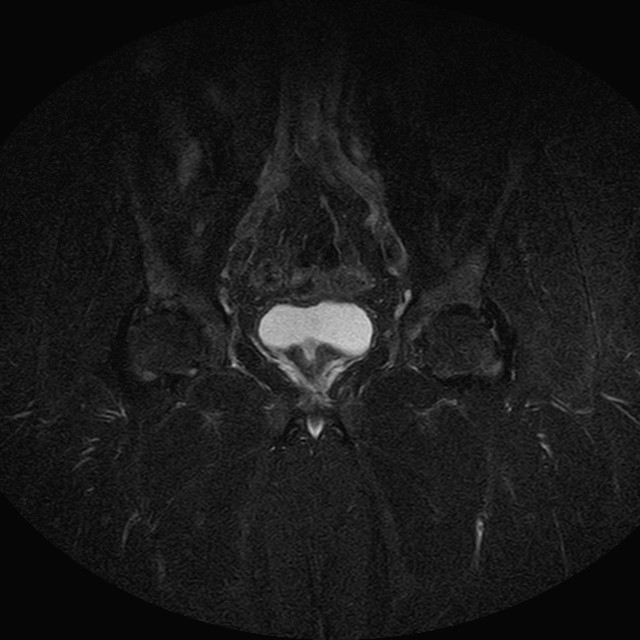

Esami: RMN BACINO

eSTIR

Evidenti e simmetriche alterazioni osteofitosiche in regione coxo femorale con riduzione delle rime articolari. Degenerazione completa del cercine glenoideo. Non attuali segni di versamento articolare. Non segni di edema osseo che escludono attuale algodistrofia od osteonecrosi. Lieve e simmetrica riduzione del trofismo della muscolatura glutea.